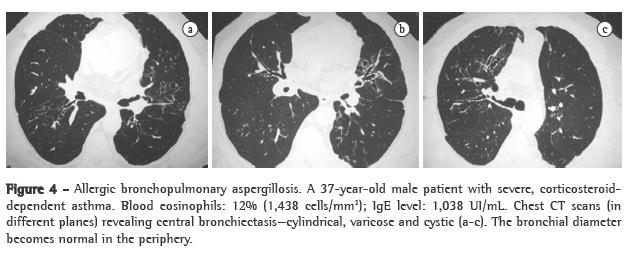

Bronchiectasis is defined as central when it is found in the medial two thirds and the bronchial diameter normalizes in the periphery.(36) It can be cylindrical, varicose or cystic (Figure 4). Expansion to the periphery in some areas or segments can occur in up to 30% of patients. In asthma patients, V- or Y-shaped opacities can indicate mucoid impaction and are suggestive of ABPA.(42,43) Mucoid impaction is defined as highly attenuated when the mucus density is higher than the skeletal muscle density.(41,44) High-attenuation mucoid impaction is also pathognomonic of ABPA and was seen in 29 (18.7%) of the 155 patients evaluated in another study.(44) Such impaction is attributed to the presence of calcium salts, metals (iron and magnesium) or products of hemorrhage in the impacted mucus. It is the same base as that of the finding of fungal sinusitis. In asthma patients, pulmonary infiltrates with foci of consolidation raise the possibility of ABPA.

Central bronchiectasis is almost pathognomonic of ABPA, assuming that cystic fibrosis and alpha-1 antitrypsin deficiency have been ruled out. In a study evaluating the CT scans of 17 patients with ABPA and 11 asthma patients with positive skin test reactivity to Aspergillus sp., but with no evidence of ABPA, bronchiectasis was found in 14 of the 17 patients and in only 2 of the 11 patients, respectively.(40) In most cases, the bronchiectasis found in the patients with ABPA was centrally distributed.

That study confirms that central bronchiectasis is an important diagnostic criterion, since it is not a common finding in asthma patients without ABPA. Asthma patients, when properly investigated, can present some degree of localized, focal cylindrical bronchiectasis, restricted to one or two lobes.

(36) In another study, which included 126 patients with ABPA, 73% of the patients were found to have central bronchiectasis, and the remaining 27% were classified as having seropositive ABPA, which is defined as asthma with positive skin test reactivity to Aspergillus sp. and positive Aspergillus sp. serology, but without central bronchiectasis.(41)